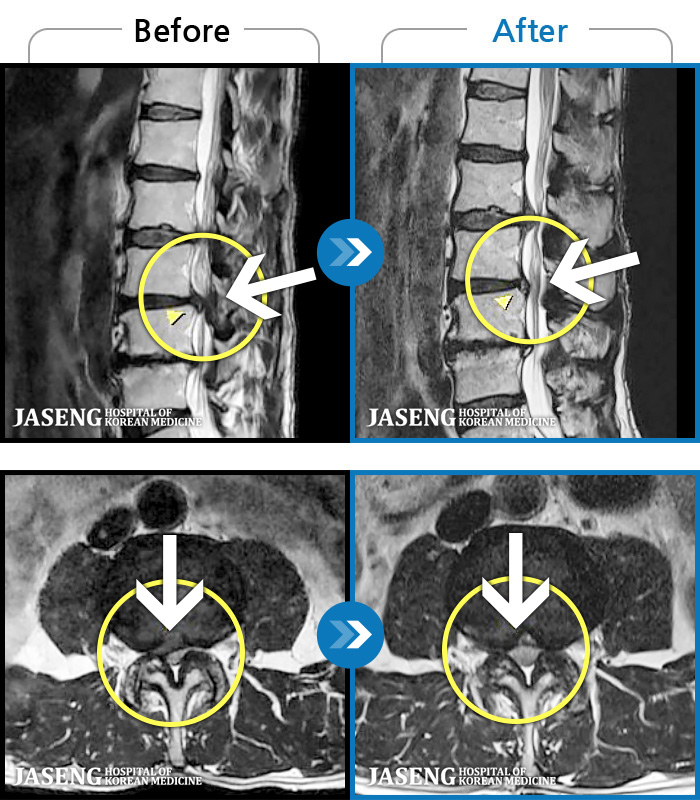

- MRI ġ

MRI ġ

1,237 MRI ũ ʸ Ȯϼ.